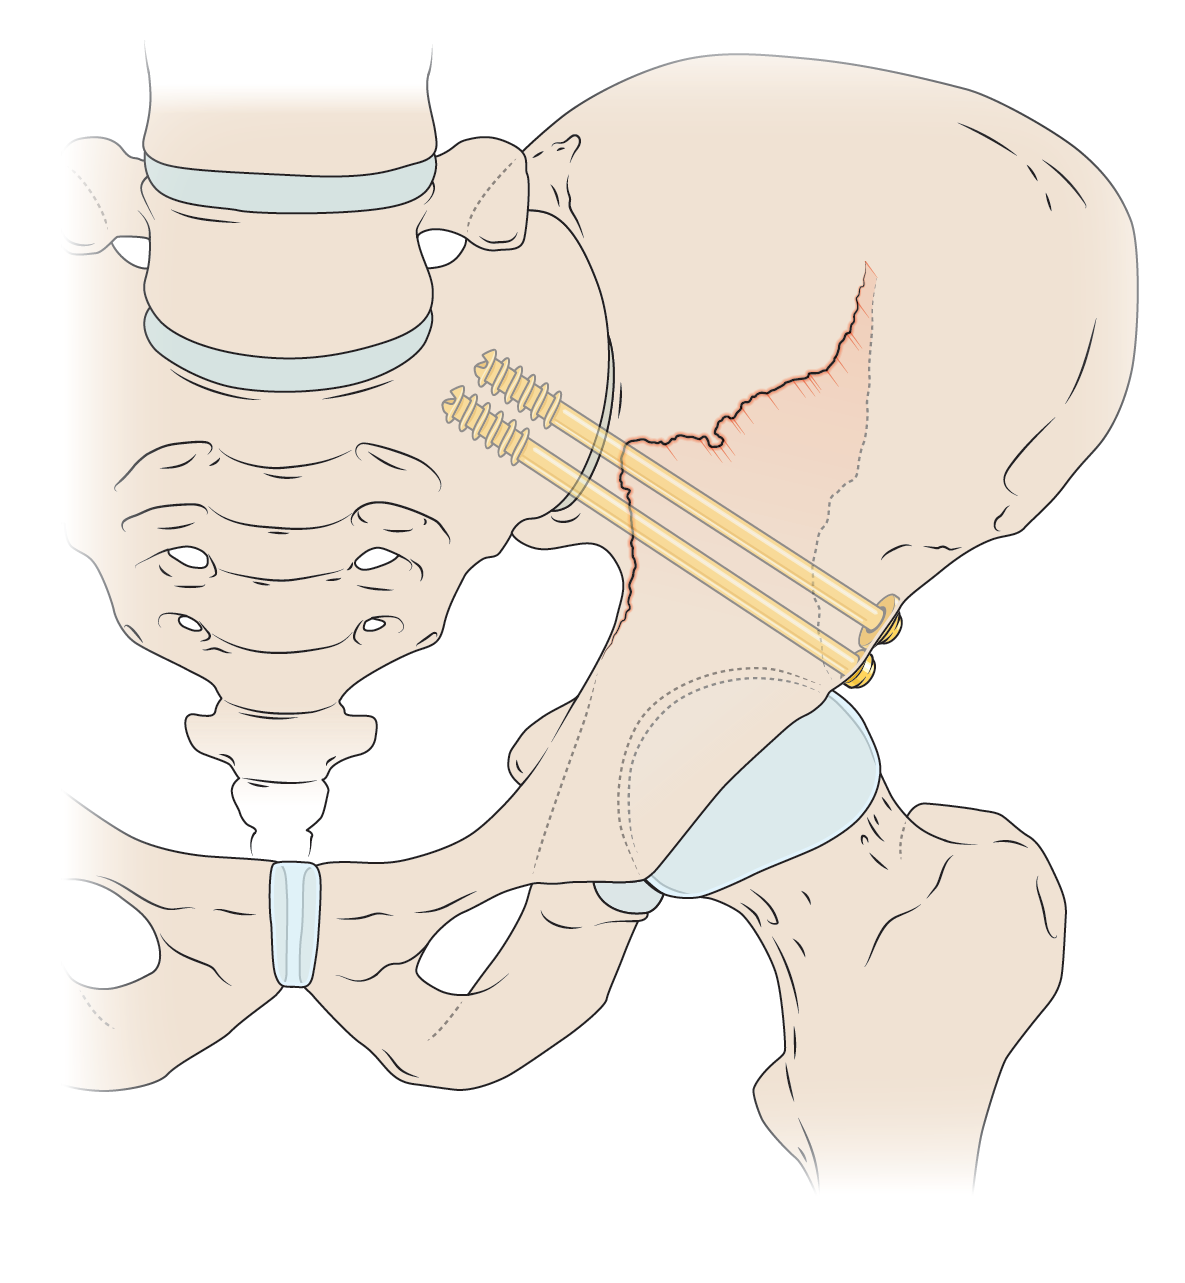

Medical-legal illustration

I can create client-specific illustrations for your personal injury or malpractice cases to both inform the jury (who often don’t have experience with hospital images) as well as gain sympathy for the affected individual. I can work directly with medical experts to ensure accuracy and admissibility in court.

Patient education

Illustrations can help patients understand surgical procedures they or a loved one are planning to have, or explain how a medication works in the body.

Licensable work

Illustrations shown below are owned by the artist and available for non-exclusive licenses, contact me for more information.